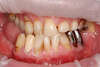

Les dents provisoires peuvent être réalisées

Situation finale